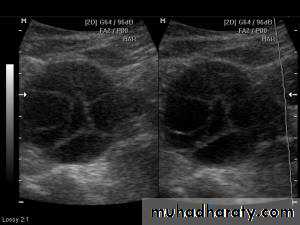

Images from women with differing expressions of the four major subtypes of the metabolic syndrome associated with polycystic ovary syndrome (A–D). The images exhibit quite differing ultrasonographic appearances in the size and distribution of follicles within PCOS ovaries. A recent corpus luteum is clearly visible in the ovary in panel (D).

• POLYCYSTIC OVARY SYNDROME